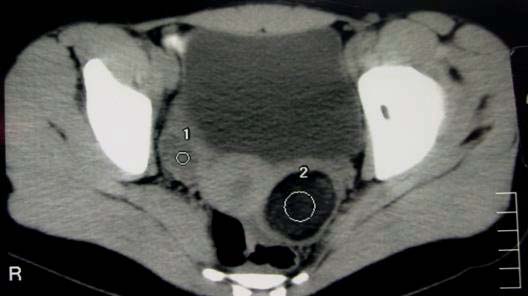

A caracterização imagiológica da lesão permitiu separar em dois grupos de acordo com o componente predominante, sólido ou líquido. Seis doentes possuíam uma lesão tumoral predominantemente quística, com distribuição equitativa pelo lado direito e esquerdo e com dimensões entre 4,7 cm e 20 cm (Figura 1).

Figura 1 - teratoma quístico

Dez doentes revelavam lesões predominantemente sólidas, localizadas preferencialmente à esquerda (6/10) e com tamanhos que variaram entre 5,5 cm e 15 cm.